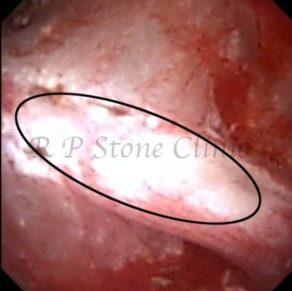

Kidney stone is a solid mass of CRYSTALS. It is the process of crystallization which initiates the formation of kidney stones. This happens in nephrons or units of kidney. Once a small crystal is formed, it can both grow & unite with other crystals leading to the formation of small concretion which eventually forms a stone. Once these large crystals detach from the collecting ducts, the process of stone formation starts in the renal collecting system. A recurrent kidney stone former is advised to know a little bit about something known as Randall’s plaque. Alexander Randall discovered plaques on the renal papillae eight decades back based on examination of 1154 pairs of autopsied Kidneys. He described these renal papillary lesions as cream colored or milk patch areas composed of calcium phosphate & calcium carbonate. These plaques could act as NIDUS for formation of KIDNEY STONE. Calcium Oxalate stone can form on this nidus & then detaches from this plaque to become a free floating stone in the collecting system of kidney

These images are taken as snap shots from the video recording of RIRS Surgery done at our hospital. These are Randall’s Plaques seen with Digital FLEX XC & Digital FLEX XC S. The cream or whitish patches are seen on the tips of RENAL PAPILLAE as seen in images below.

Randall’s Plaques may lead to the formation of Stones.